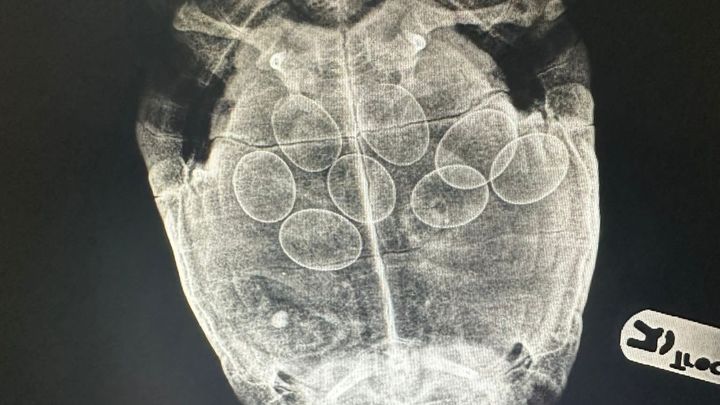

Shelly is our much-loved school tortoise. She had been unwell for a few days so we took her to the vet. After an examination and an x-ray, we found out Shelly has 8 eggs inside of her. After lots of medication and a few days at the vets, she managed to lay all but one egg. She has come home with her medication and is going to have to go back to the vets next week for an operation to remove the final egg. This is going to be a very expensive process and any donations towards the cost would be greatly appreciated.